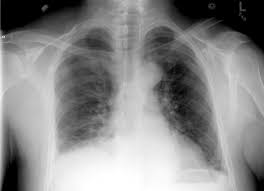

The condition spans all age groups, and ems providers should, therefore, maintain a high index of suspicion for pneumothorax for any patient with a. Tap on/off image to show/hide findings. However, treatment is reliant on timely review of radiographs. If you cannot diagnose a tension pneumothorax at medical finals you won't find an examiner who will defend you. A normal or raised paco 2 is concerning as it indicates that the patient is tiring and failing to ventilate effectively. Ipsilateral pleural line with reduc ed/absent lung markings (i.e., increased transparency) abrupt change in radiolucency; Pneumothoraces may be small or very large. In this video, you'll learn how to identify when radiological pleura is abnormal and the key signs to look out for when trying to diagnose a pneumothorax.

Finding of pneumothorax on chest radiographs may include the following: The condition spans all age groups, and ems providers should, therefore, maintain a high index of suspicion for pneumothorax for any patient with a. Pneumothorax describes gas within the pleural space. Hover on/off image to show/hide findings. Clinical signs of a tension pneumothorax in the ventilated patient are comparably rapid, with arterial and mixed venous peripheral capillary oxygen saturation immediately decreasing 5.

Hover on/off image to show/hide findings. Finding of pneumothorax on chest radiographs may include the following: Typical abg findings in pneumothorax include low pao 2 and low paco 2 (due to hyperventilation). A pneumothorax refers to the presence of gas or air in the pleural space. This may occur because of a number of reasons and may be spontaneous. The video is an effort to revisit the pneumothorax. Pneumothorax describes gas within the pleural space. Schematic illustration of the radiographic findings and differences between pneumothorax and artifacts related to skinfolds.